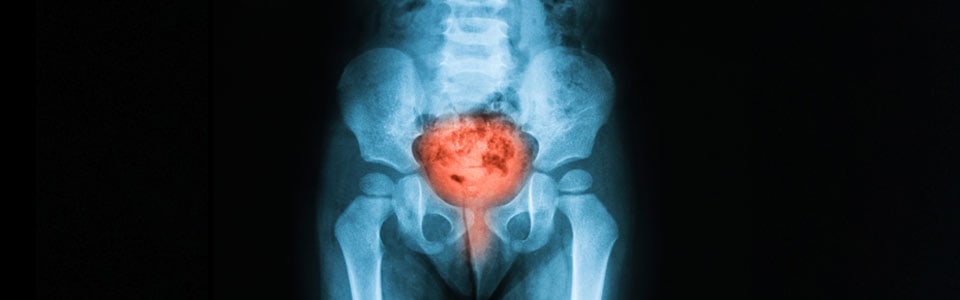

Семейное положение влияет на выживаемость при раке мочевого пузыря

Рак мочевого пузыря является девятой наиболее распространенной злокачественной опухолью во всем мире, уротелиальная карцинома — наиболее распространенный подтип. Установлено, что семейное положение влияет на показатели выживаемости по многим опухолям. Онкобольные, находящиеся в браке, имеют лучшую выживаемость при колоректальном раке, раке желчного пузыря и предстательной железой, а также при карциноме молочной железы.